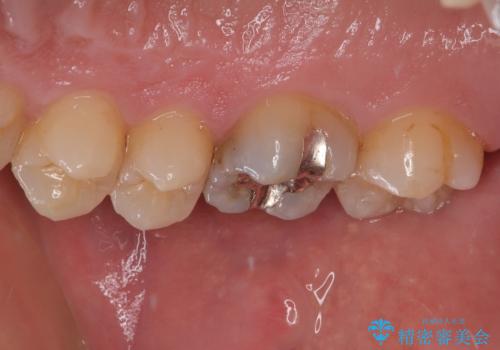

- 舌で触ると段差が気になるとのことで来院された患者様です。歯質がわずかに欠けており金属の詰め物の間に小さなギャップが生じていました。

咬み合わせも強い方なので物性、適合性に優れたゴールドインレーにて治療をしていくことになりました。

拡大鏡視野下で金属の詰め物、虫歯を除去し、ゴールドインレーに適した形に整えました。